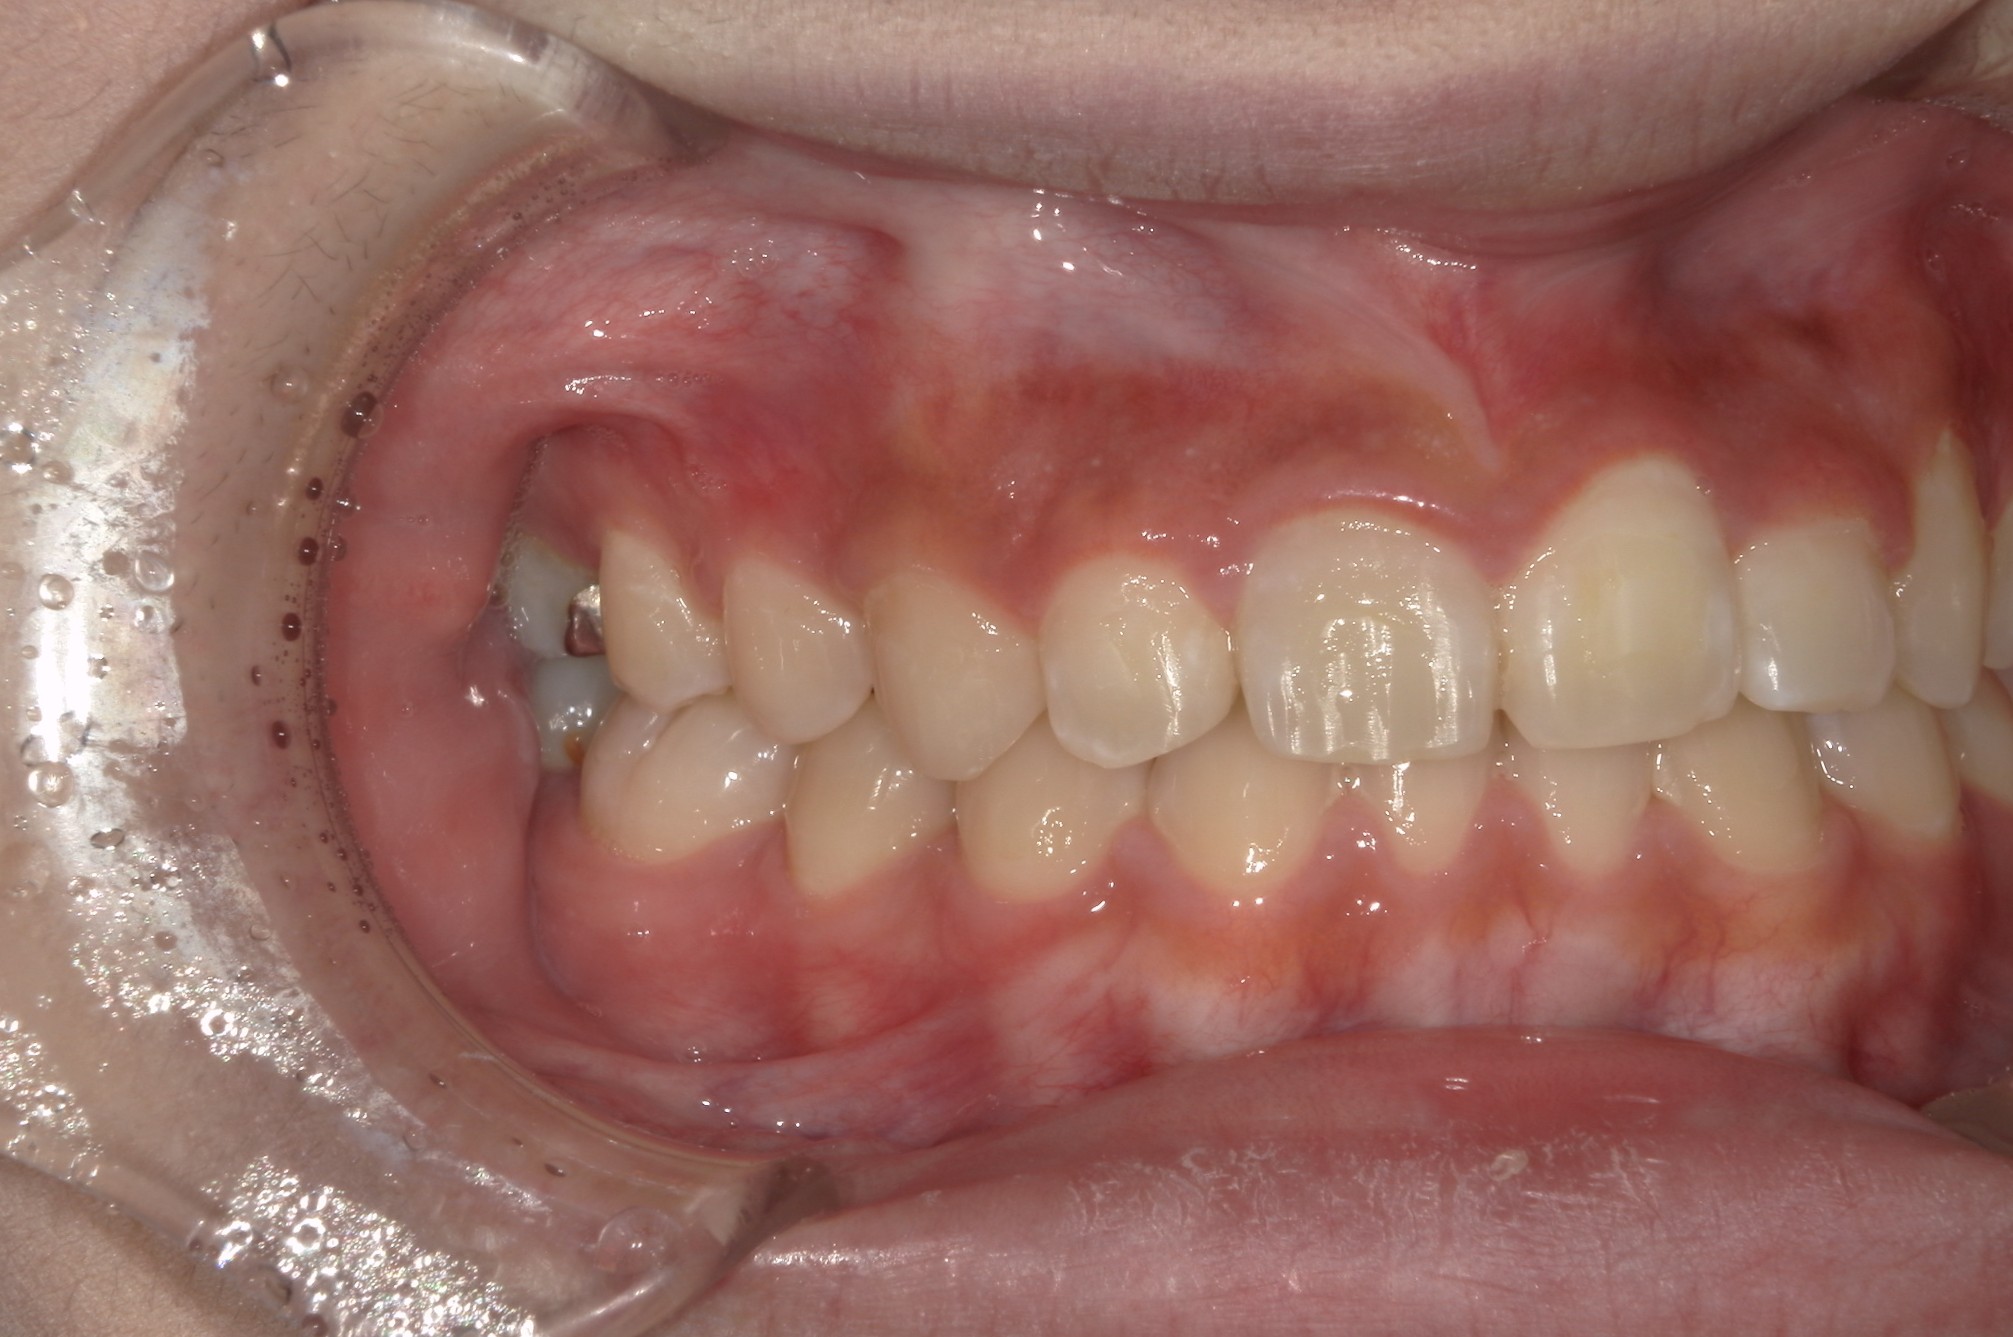

矯正術前:左側

| 主訴 | 上の歯が1本だけ奥に引っ込んでいることが気になる |

| 治療内容 | 患者様は、上の歯が1本だけ奥に引っ込んでいることを気にされており、矯正検査後Ⅱ級傾向の叢生と診断いたしました。ワイヤー矯正後に、インビザラインによる仕上げ矯正を行っております。 |